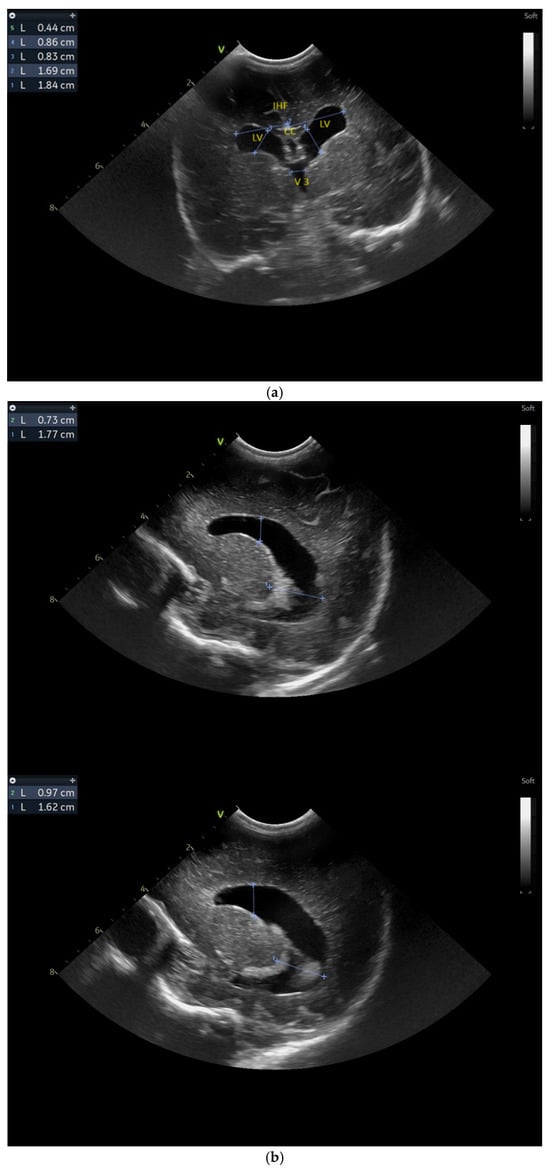

The day one of life CUS revealed the presence of a left frontal conatal cyst with no other modification (Figure 2a).

Figure 2.

(a) Day one. Cranial ultrasound. Sagittal view. A left frontal conatal cyst can be observed. IHF—interhemispheric fissure. CG—cingulate gyrus. CC—corpus callosum. CSP—cavum septum pellucidum. TCG—thalamic-caudate groove. MF—Monroe foramina. SF—Sylvian fissure. Yellow arrow—conatal cyst (personal image collection). (b) Day three. Cranial ultrasound. Coronal view. Bilateral ventricular dilatation. Yellow arrows—hyperechoic images can be seen at the level of the thalamic-caudate groove and within the ventricles (personal image collection). (c) Day three. Cranial ultrasound. Coronal view. Orange arrows—bilateral periventricular hyperechoic images (personal image collection). (d) Day three. Cranial ultrasound—Doppler examination. Sagittal view. CC—corpus callosum. FL—frontal lobe. LV AH—lateral ventricle anterior horn. V 3—third ventricle. V 4—fourth ventricle. OL—occipital Lobe. Yellow arrow—presence of color Doppler signal within the Sylvian aqueduct (personal image collection). (e) Day 19. Cranial ultrasound. Sagittal view (left). Yellow arrows—conatal cysts. Pink arrows—PVL lesions (personal image collection). (f) Day 19. Cranial ultrasound. Sagittal view (left). Yellow arrows—conatal cysts. Pink arrows—PVL lesions (personal image collection). (g) Follow-up examination at term corrected age. Cranial ultrasound. Coronal view. Slight dilation of the lateral ventricles. IHF—interhemispheric fissure. CG—cingulate gyrus. CC—corpus callosum. CSP—cavum septum pellucidum. LV—lateral ventricle. MF—Monroe foramina (personal image collection). (h) Second follow-up examination. Cranial ultrasound. Coronal view. Dilation of interhemispheric fissure and subarachnoid space. D1—sinus–cortical width measurement. D2—interhemispheric width measurement. D3—cranio-cortical width measurement (personal image collection). (i) Third follow-up examination. Cranial ultrasound. Coronal view (left). D1—dilation of interhemispheric fissure. D2, D3—Levine index measurement (personal image collection). (j) Cranial ultrasound. Sagittal view (right). Normal brain structures (personal image collection). (k) Head circumference-for-age. “X” symbols represent the measurements performed from birth and follow-up examinations (personal image collection) [28].

On day three of life, the CUS displayed a bilateral germinal matrix hemorrhage with more than 50% of the ventricular volume being occupied by blood. Periventricular hyperechoic images could be observed as well (Figure 2b,c).

On the fourth day of life, a Doppler examination showed the presence of a signal within the third ventricle (Figure 2d).

A series of four lumbar punctures were performed during the patient’s in-stay to relieve the intracranial pressure—expressed as a bulging fontanelle. The first three lumbar punctures presented hemorrhagic CSF, while the last lumbar puncture showed sero-citrine CSF. Afterwards, the ventricular dimensions stabilized; however, small visible PVL lesions were visible on the CUS examination, in addition to the two conatal cysts that were observed (Figure 2e,f).

The first follow-up CUS examination was performed at the term-equivalent age (corrected gestational age) and revealed a slight dilation of the lateral ventricles (Figure 2g). The neurologic examination showed normal development for the corrected gestational age and mild plagiocephaly.

The next follow-up examination was performed two months from birth at the term-equivalent age and the CUS examination showed dilation of the interhemispheric fissure and the subarachnoid space (Figure 2h). Plagiocephaly, torticollis, mild motor development delay, and hypertonia in the lower limbs were observed.

Four months after the first follow-up examination, the CUS revealed normal brain structures. The general movement examination showed absent fidgety movements, while the neurological examination showed a global developmental delay with hypertonia of the limbs predominantly at the level of the left side of the body (Figure 2i,j).

On the fourth follow-up examination, the dilations were still visible. The neurological examination revealed mild trapezius muscle retraction and mild hypertonia at the level of the inferior limbs. The fifth follow-up examination—performed at one year after birth—revealed mild motor developmental delay.